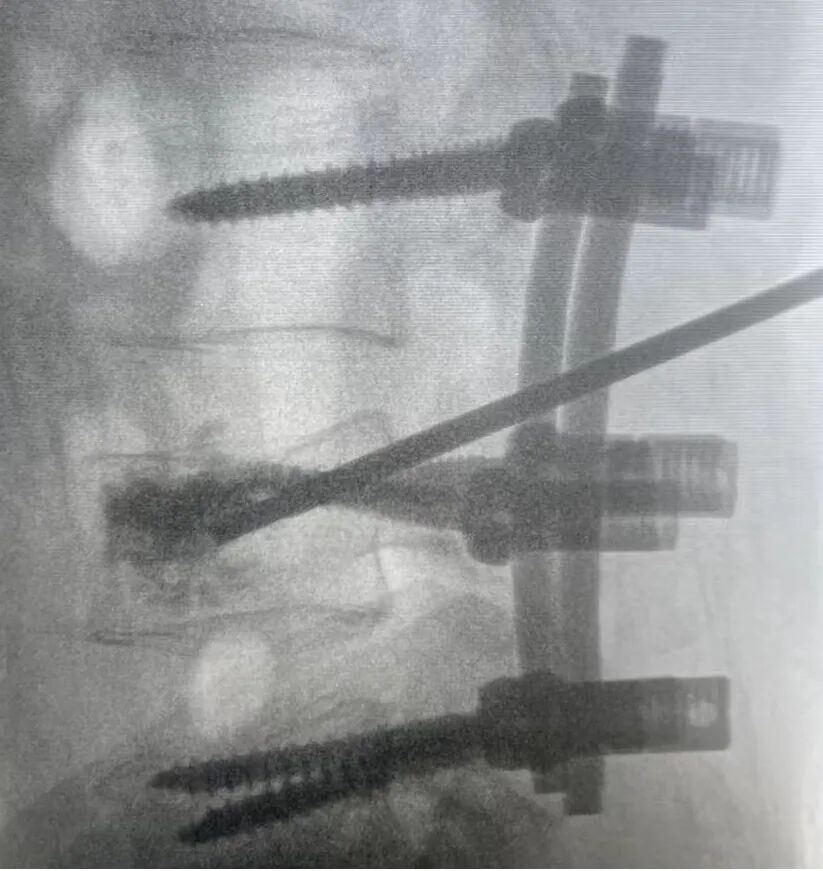

近日,在“国庆”来临之际,援川专家李国庆医生带领盐源县人民医院骨科团队顺利完成了攀西地区首例“后路肌间隙入路短节段固定联合伤椎椎弓根基底部外上缘入路PKP术”。

患者杜某,55岁,因外伤导致腰4椎体爆裂性骨折,入院完善相关检查后,诊断为“腰4椎体爆裂性骨折合并骨质疏松症”。随后援川专家李国庆医生与盐源县人民医院骨科万喜顺副主任及相关医护人员展开了术前讨论,为杜某制定手术方案。李国庆医生考虑患者椎体压缩明显,并且合并有骨质疏松,如果单独采用“后路椎弓根螺钉内固定”技术容易出现内固定失败,椎体再次压缩等情况发生,如果单独采用PKP手术的方式容易出现椎体高度复位不佳或骨水泥渗漏造成严重并发症。

两种手术方式对于杜某而言,都不是最佳的治疗方式。因此,经过讨论后,李国庆医生决定采用“后路肌间隙入路短节段固定联合伤椎椎弓根基底部外上缘入路PKP术”手术过程非常顺利,杜某在术后的第二天就开始了功能锻炼,恢复良好。

术中透视显示患者椎体已复位

骨水泥分布良好